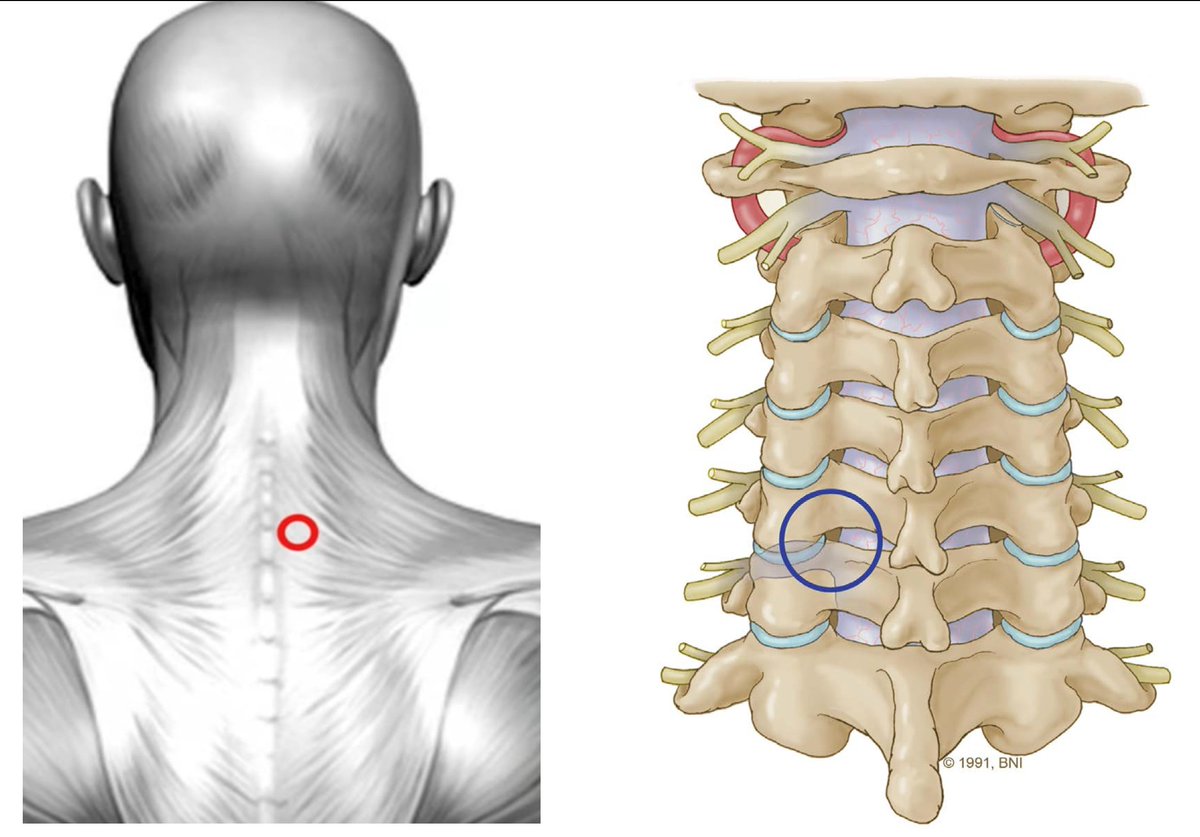

🔟MIS cervical foraminotomy تحرير الأعصاب العنقية

المشاكل المتعلقة بالانزلاق الغضروفي الضاغط على الأعصاب العنقية تعالج غالبًا عن طريق جرح في أمام الرقبة، ولكن هناك بعض الحالات تحتاج إلى تحرير العصب من الخلف، ومن التقنيات الحديثة هو استخدام تقنية الأنبوب من خلال جرح صغير في خلف

1⃣1⃣

الرقبة لتوسيع القناة العصبية وتحرير العصب.